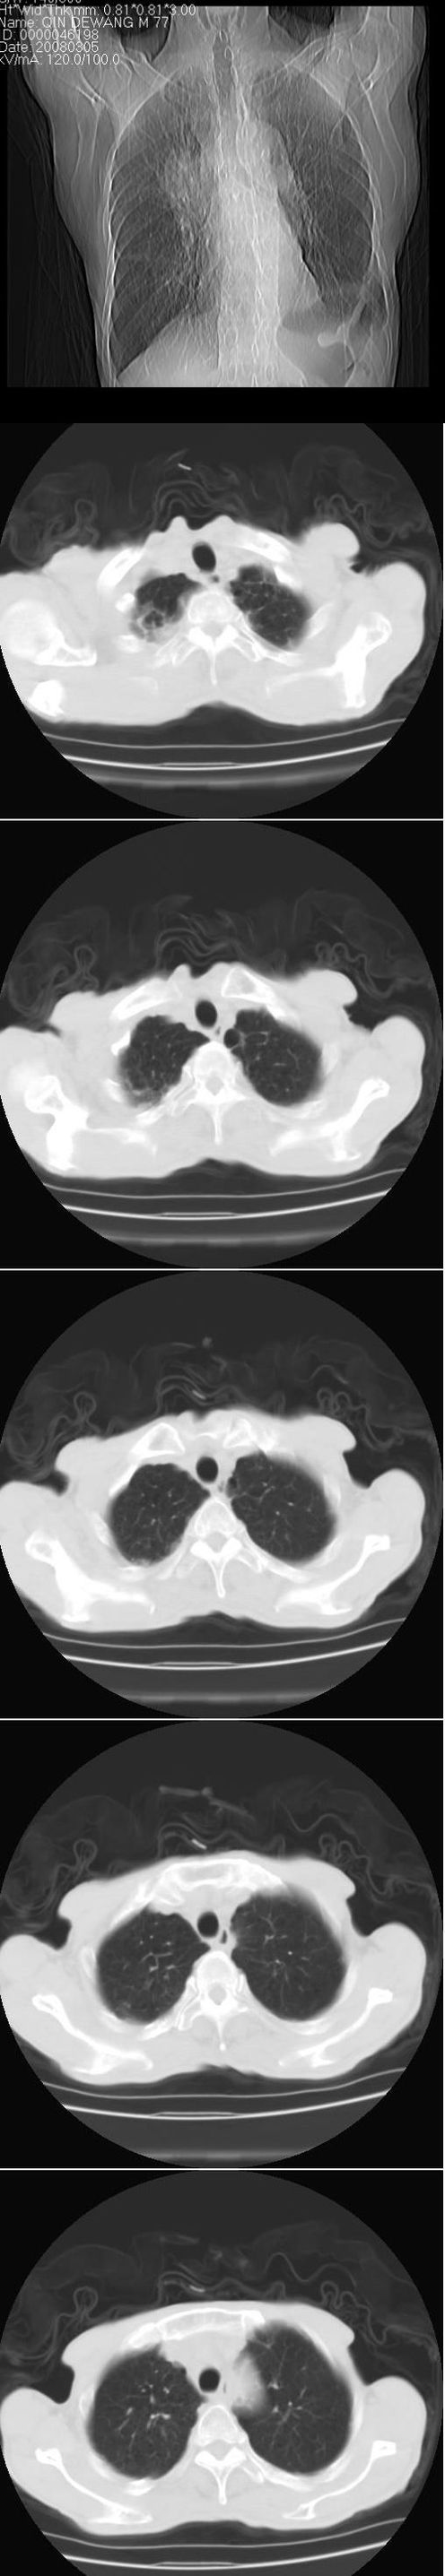

标题: CT12024:男,77岁。咳嗽两月余,气喘一月,13年前岑作贲门 [打印本页]

标题: CT12024:男,77岁。咳嗽两月余,气喘一月,13年前岑作贲门

1、右侧中心型肺癌,右肺门,纵隔淋巴结转移可能性大。

2、贲门癌术后所见。

右侧中心型肺癌,右肺门,纵隔淋巴结转移。

右中心型肺癌 纵隔淋巴结转移

右侧中央型肺癌伴右肺门及纵隔淋巴结转移.

1 右肺中心型肺癌伴右肺门及纵隔淋巴结转移.

2  左肺贲门癌术后改变.

1)考虑为:右侧中心型肺癌并右肺门及纵隔淋巴结转移。2)贲门癌术后改变。